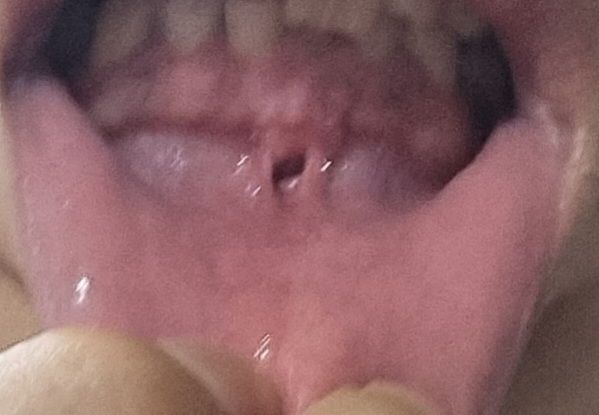

구내염인건가요?

원래는 하얗게 오돌토돌하게 자리잡은지 오래되었는데

잠결에 치아로 깨물었더니 사진처럼 검은색 구멍이 생겼습니다.

사진이 선명하지 못하여 정확한 판단은 어렵습니다만 일반적으로 보이는 구내염의 소견은 아닙니다. 실제로 점막에 천공이 생긴 것 같은데 관련하여서는 정확하게는 진료를 받아보시는 것이 필요해 보입니다. 이비인후과 및 치과 진료를 받으시길 권고드립니다.